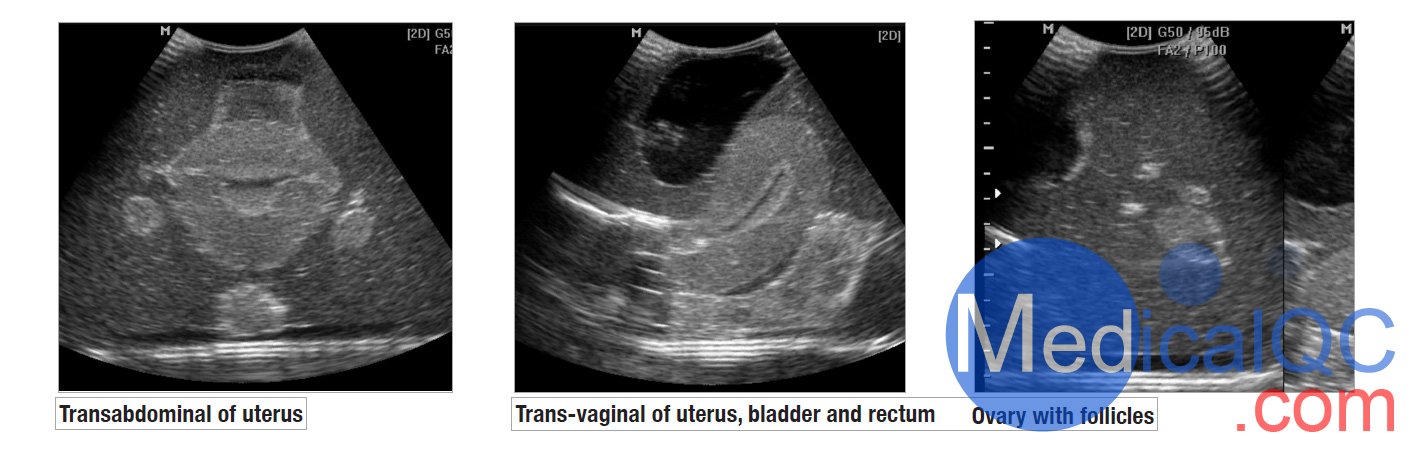

CIrs 404A女性盆腔模體,CIrs 404A超聲訓(xùn)練骨盆模體超聲影像圖:

CIrs 404A女性盆腔模體,CIrs 404A超聲訓(xùn)練骨盆模體影像圖

我們的CIrs 404A女性盆腔模體,CIrs 404A超聲訓(xùn)練骨盆模體由一個外部女性盆腔模型組成,其中包含用于掃描的子宮、輸卵管、卵巢、膀胱和直腸標(biāo)志。體模具有腹部和陰道掃描通道,允許各種換能器方向。

外部解剖

腹部和陰道掃描通路

子宮內(nèi)膜和子宮肌層

有卵泡的卵巢

滿膀胱

直腸標(biāo)志物